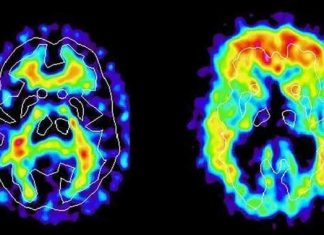

Envejecimiento cerebral acelerado por 10 años en la mediana edad con...

Tener sobrepeso u obesidad en la mediana edad puede envejecer el cerebro por alrededor de 10 años. Esta es la conclusión de un nuevo...